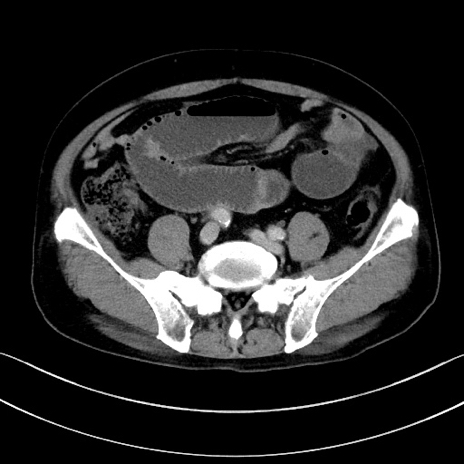

症例15(横断像)

【症例】70歳代男性

【主訴】腹痛

【現病歴】今朝から腹痛あり。全体的に痛い。特に左上の方。排ガスが今日はない。冷や汗が出る。

【既往歴】直腸癌術後

【身体所見】左側腹部〜上腹部に圧痛あり。腹膜刺激症状明らかなではない。軽度反跳痛。左下腹部に術後瘢痕あり。

【データ】WBC 7700、CRP 0.02